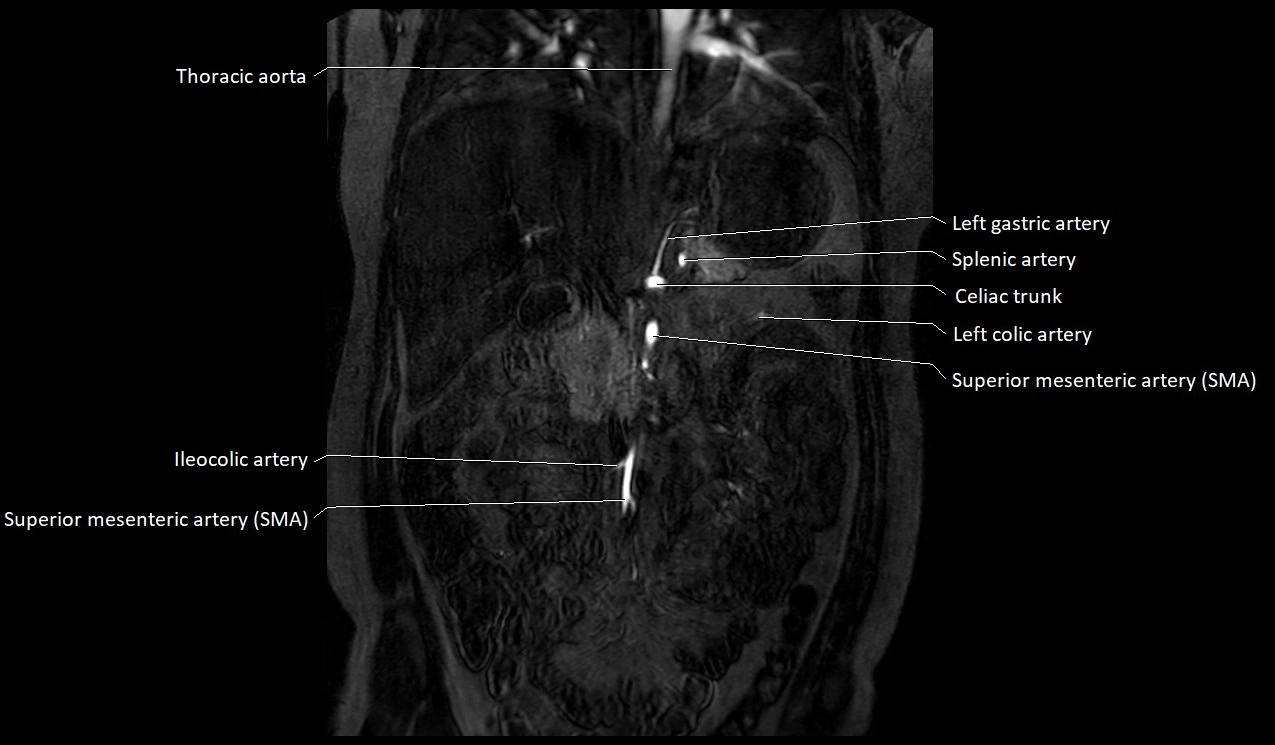

MRI Appearance

T1-weighted images:

Artery appears as a small linear hypointense flow void coursing over the superior pubic ramus

Seen within bright perivascular fat of pelvis

T2-weighted images:

Artery lumen is a signal void

In thrombosed or diseased variants, lumen may appear hyperintense relative to surrounding fat

STIR:

Fat suppression makes the artery more visible within pelvic fat

Helps identify perivascular edema, hematoma, or inflammatory changes

T1 Post-Gadolinium (with fat suppression):

Artery enhances brightly and homogeneously

Useful for tracing the course, anastomoses, and presence of corona mortis

Highlights arterial wall thickening or tumor encasement if present

MRA Pelvis with Gadolinium:

Clearly delineates the origin, course, and anastomoses of the accessory obturator artery

Identifies connection with inferior epigastric artery, external iliac artery, or obturator artery

Excellent for detecting vascular variants prior to surgery

Useful in mapping pelvic vasculature in trauma, tumor embolization, or preoperative planning